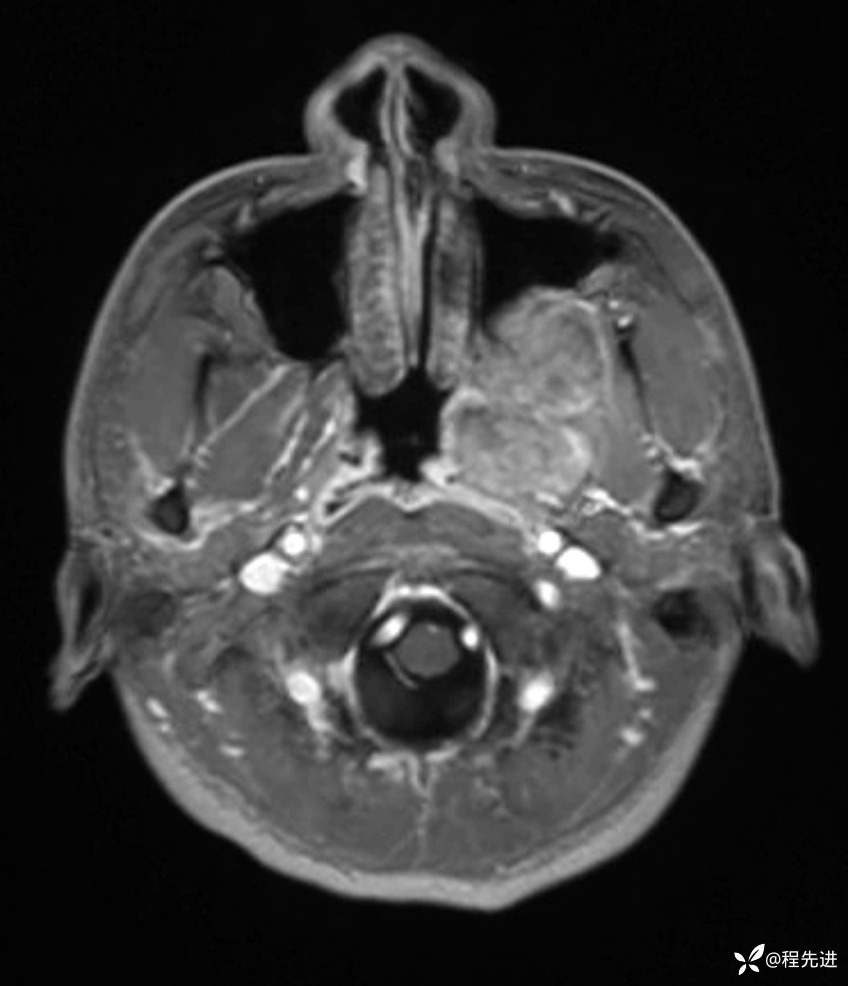

T1增强: